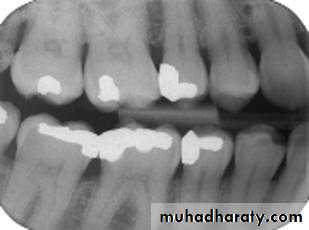

Premolar bitewing. A, Film placement. B, Resultant radiograph.

AB

The molar-bitewing. A, Film placement. B, Resultant radiograph.

A

B